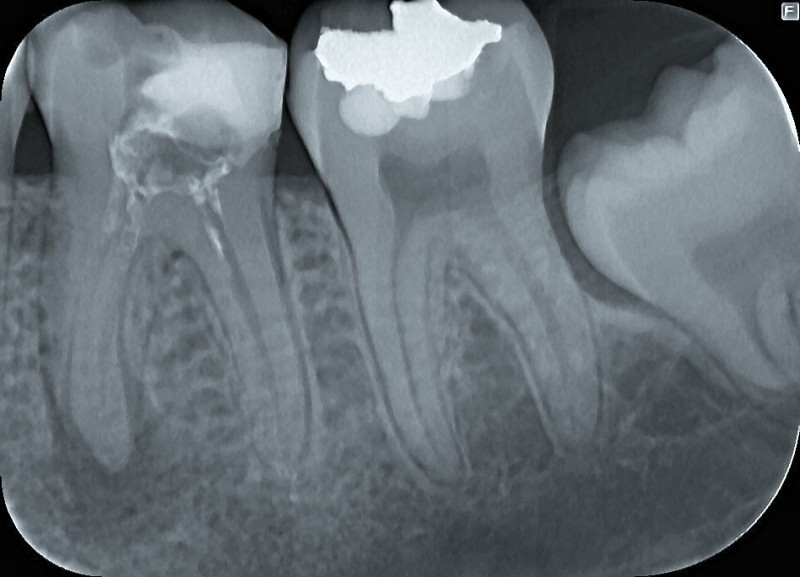

- parodontalno ter endodontsko zdravljenje,

Redni pregledi omogočajo zgodnje odkrivanje kariesa, bolezni dlesni in drugih težav, še preden povzročijo bolečino ali zahtevnejše posege. S pravočasnim ukrepanjem lahko ohranimo več zdrave zobne strukture, zmanjšamo stroške zdravljenja ter dolgoročno poskrbimo za boljše ustno in splošno zdravje. Naša dobra zobozdravstvena ordinacija (Slovenija) z veseljem poskrbi tako za preventivo kot za zdravljenje že nastalih bolezni. Kontaktirajte nas za pregled oziroma za posvetovanje.